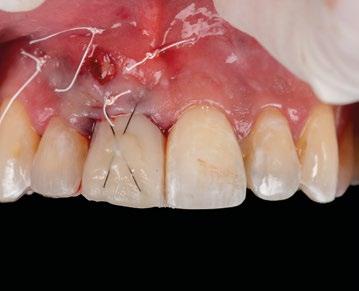

1.- Quitamos la corona ferulizada. (Figura 15)

2.- Extraemos de manera meticulosa la raíz del diente afectado. (Figura 16)

3.- Legramos toda la zona del lecho implantario con el fin de poder eliminar cualquier resto de tejido de granulación.

4.- Desepitelizamos en margen gingival. (Figura 17)

5.- Tunelizamos el defecto vestibular para alojar el injerto de tejido conectivo. (Figura 18)

6.- Colocamos injerto de tejido conectivo. (Figura 19)

7.- Interponemos membrana reabsorbible entre tejido conectivo y alveolo. (Figuras 20 y 21)

8.- Realizamos osteotomía mediante férula quirúrgica utilizando fresa piloto. (Figuras 22 a 24)

9.- Seguimos preparando el lecho utilizando fresado biológico con la OsseoShaperTM. (Figura 25)

10.- Colocamos implante Nobel Biocare N1TM TiUltra de 3,5x13. (Figura 26)

11.- Observamos el torque obtenido de 50N por lo tanto podemos realizar carga inmediata. (Figura 27)

12.- Colocamos aditamento N1TM Base XealTM con el fin de trabajar la prótesis a nivel gingivall. (Figura 28)

13.- Colocamos pilar provisional.

14.- Rellenamos el gap con creos xenogainTM, compactando para que el hueso llegue lo más apical posible y cubra la superficie implantaria expuesta. (Figura 29)

15.- Cortamos pilar provisional y adaptamos el TempShellTM con composite. Podemos comprobar la predictibilidad en cuanto a la posición 3D planificada de nuestro implante. (Figuras 30 a 32)

16.- Colocamos restauración provisional atornillada y fuera de oclusión y traccionamos hacia coronal de los tejidos. (Figura 33)